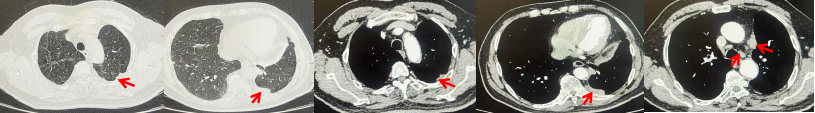

2024.11.19患者出现右侧胸痛,复查胸部CT检查示右侧胸膜肿物,大小约31mmX24mm,右侧4、5肋骨骨质破坏,考虑转移(如图2)。建议患者穿刺活检取病理明确诊断,患者拒绝,经MDT会诊后结合影像学表现及病史考虑为胸膜转移,肋骨转移,分期为rT0N0M1a IVA期,DFS仅仅17个月。2024.12.05起行信迪利单抗联合培美曲塞+卡铂方案治疗4周期,复查胸CT评效PR(如图3)。之后给予信迪利单抗+培美曲塞维持治疗6周期,期间复查CT评效PR(如图3)。目前信迪利单抗+培美曲塞维持治疗中,截止至目前PFS约为8个月,治疗期间未出现明显毒副反应。

图2:患者胸膜及肋骨转移(2024.11)胸部CT肺窗、纵隔窗及骨窗